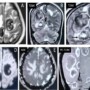

•MRI brain reveals multiple intra axial T2 hypointense lesions marginated by T2 hyperintense rim encircling the lesion brighter than the surrounding edema with significant perilesional edema (Figure: A to C). It is evidently made in the lesion in the right parietal lobe (Arrows in Figure: C).

•Post contrast study demonstrates thick peripheral enhancement (Figure:F).

•DWI -ADC images demonstrating no restricted diffusion (Figure: D & E).

•Screening CT thorax demonstrates a large mass in the right lung lower lobe (Figure:G).